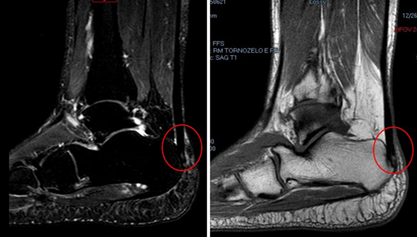

The achilles tendon is one of the most important and strongest tendons in the body. This tendon is formed by the union of the gastrocnemius and soleus muscles with insertion into the calcaneal bone. The triceps sural muscle plays a role in the knee and ankle joint, participating in knee flexion and ankle plantar flexion movements with important role in gait and in other functions involving the ankle and foot. Although achilles tendon has some particularities and peculiarities, the pathophysiology of the achilles follows the same precepts as the other tendons in the body; being able to be acute or chronic, as well as affecting athletes and non-athletes (Figure 1).1–3

Figure 1 Illustration of achilles tendon tendinopathy. Thickening with longitudinal streaks of signal alteration due to tendinosis is observed in the insertion of the lateral half of the achilles tendon, associating a spur outline with mild medullary edema in the calcaneal tuberosity.